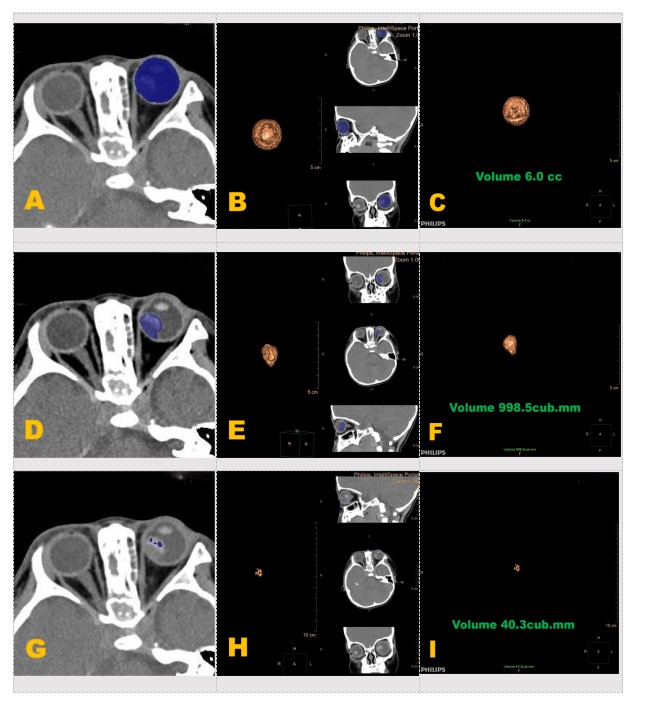

图3 分期影像特征示图

Figure 3 Diagram of staging CT imaging features

图2容积测量步骤示图

Figure 2 Diagram of volume - measurement steps